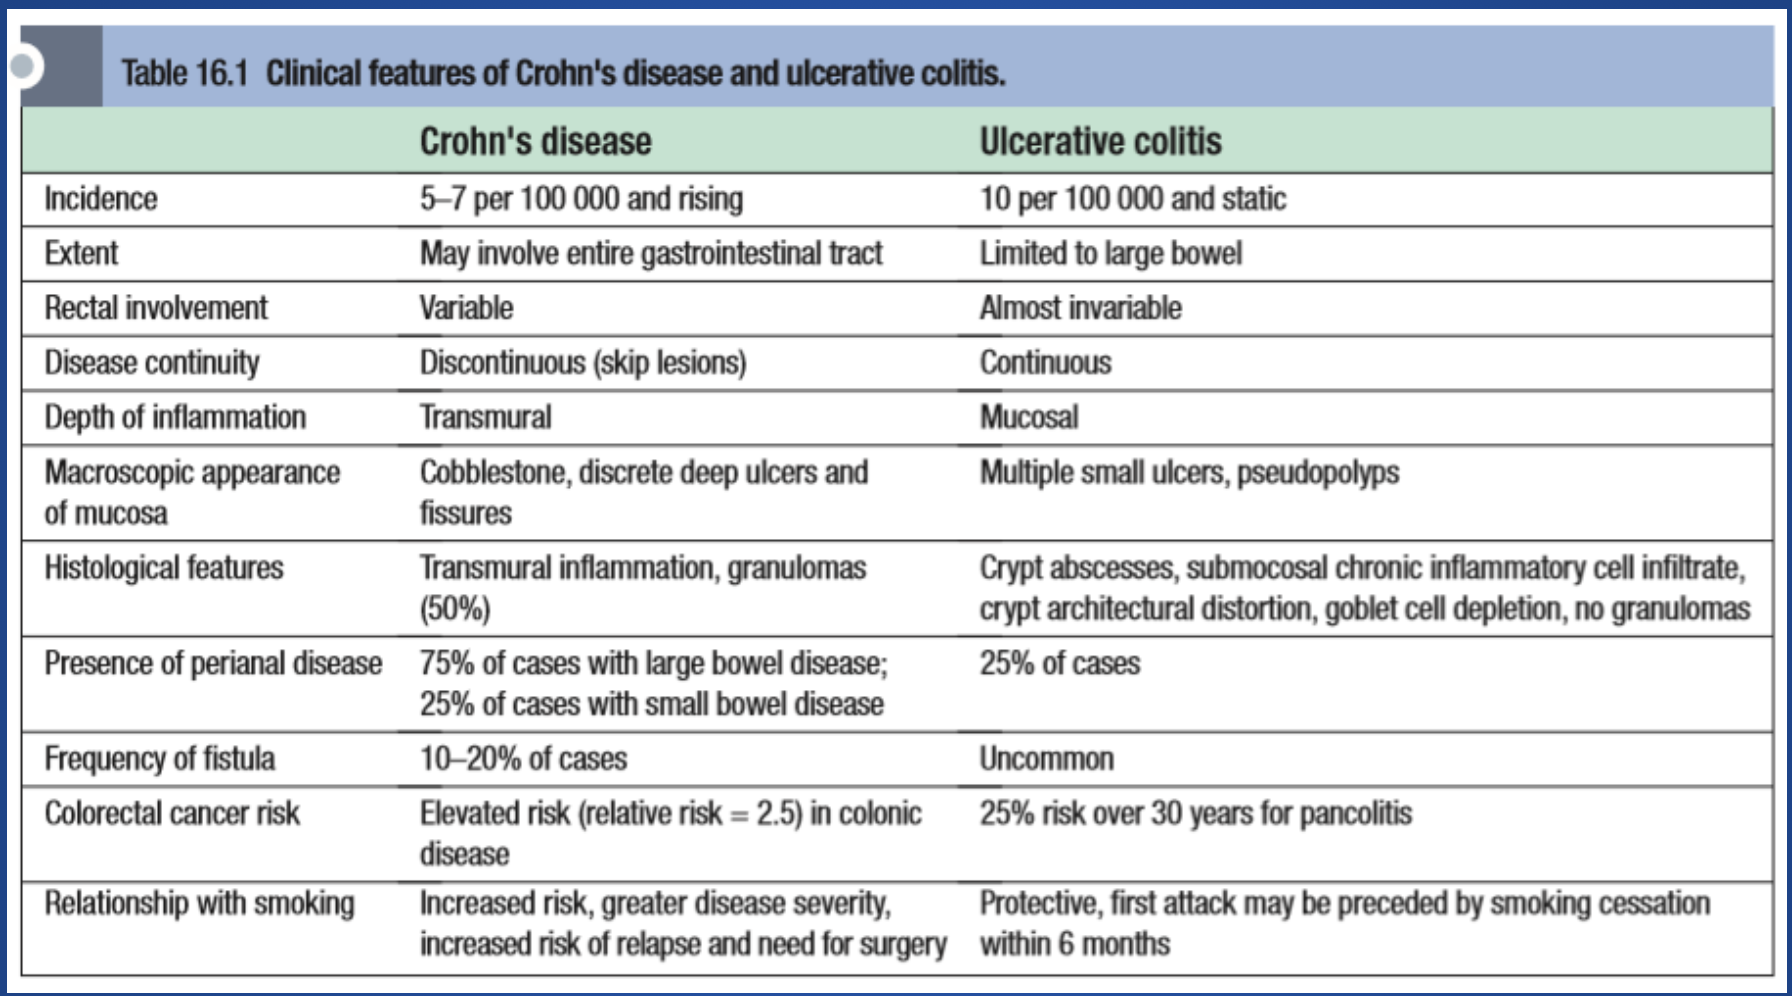

Comparison of Crohn’s Disease (CD) and Ulcerative Colitis (UC)

| Feature | Crohn’s Disease (CD) | Ulcerative Colitis (UC) |

|---|---|---|

| Location | Any part of the GI tract, mouth to anus, skip lesions | Colon and rectum only, continuous lesions |

| Depth | Transmural (all layers of bowel wall) may result in ulcers, transmural ulcers, resulting in fistula formation | Mucosa and submucosa only - rarely presents as feature of fistula formation |

| Inflammation | Patchy, granulomatous | Diffuse, continuous |

| Symptoms | Abdominal pain, diarrhea, weight loss, fatigue, fever | Bloody diarrhea, urgency, tenesmus, abdominal pain |

| Complications | Strictures, fistulas, abscesses, perianal disease | Toxic megacolon, perforation, colorectal cancer risk |

Table Comparision

| Feature | Ulcerative Colitis | Crohn Disease |

|---|---|---|

| Extent | Only colon involved | Panintestinal |

| Inflammation Pattern | Continuous, extending proximally from rectum | Skip-lesions with intervening normal mucosa |

| Depth of Inflammation | Mucosa and submucosa | Transmural |

| Perianal Lesions | Absent | Present |

| Granulomas | Absent | Noncaseating granulomas present |

| Bleeding | Common | Uncommon |

| Fistulae | Rare | Common |